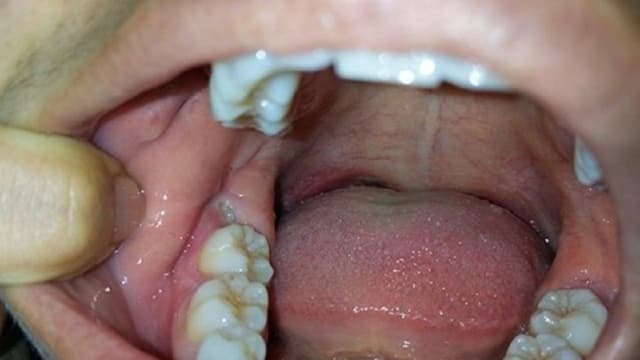

Nguyên nhân bị sưng lợi trong cùng, triệu chứng và cách điều trị

Sưng lợi trong cùng là một tình trạng không hiếm gặp, đặc biệt là ở những người trưởng thành đang trong quá trình mọc răng khôn. Mặc dù nhiều người có thể cho rằng đây chỉ là một triệu chứng bình thường và sẽ tự hết sau một thời gian, nhưng thực tế,  bị sưng […]